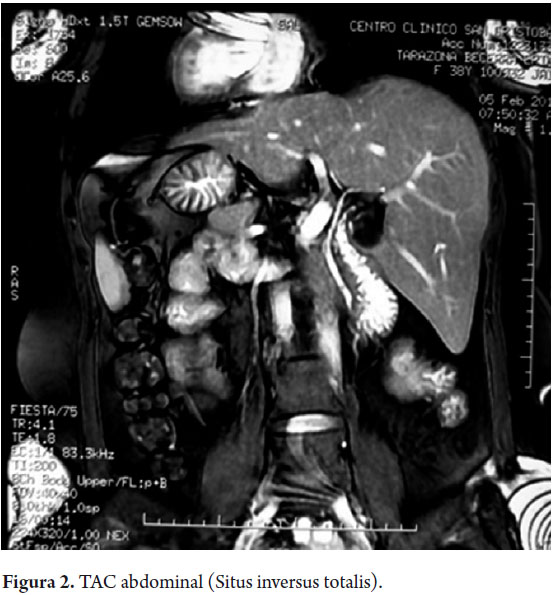

Se solicita TAC abdominal corroborando situs inversus totalis (figura 2). En la colangiorresonancia se aprecia discreta dilatación de colédoco distal con dos imágenes de defecto en su interior (figura 3).